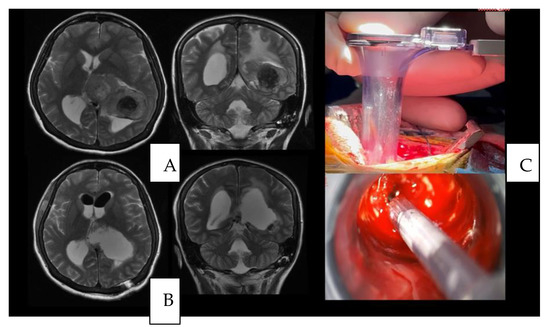

4.1. Case 1